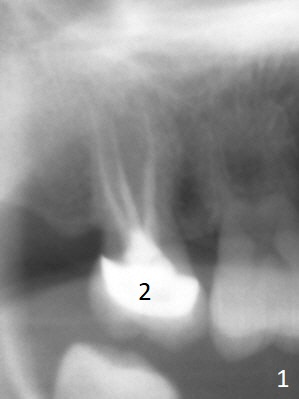

A 58-year-old woman has had RCT done at #2 for several years. The roots are trifurcated with sufficient bone height (Fig.1-3). Recently the tooth becomes symptomatic with formation of a distal fistula (Fig.4). After extraction, the septum (Fig.5 S) may be wide enough for initial drill (Fig.6). If not, resection the thin part of the septum (Fig.7 red line, with small or medium Rongeur) and use the initial drill (Fig.8). Anyway, take PA immediately to avoid sinus membrane perforation. If possible, adopt single drill technique.